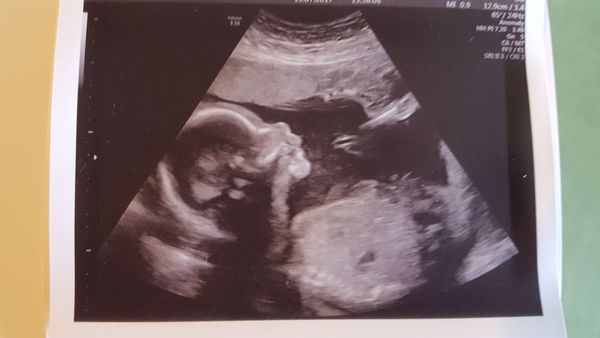

Motherhippy16 · 15/07/2017 08:01

Good morning all. Sorry if I don't comment on recent posts as my phone doesn't load up properly until I post something! We had our 20 week scan on Thursday and it's a little boy!!!! He is well and healthy with a small head and round tummy (just like his daddy!) And am feeling so many flutterings esp in the eve. He was kicking and moving and stretching like anything in the scan so pleased to know even though I can't feel it that he's dancing around! Much love to all and hope you are all well x x x x

What a lovely scan @Motherhippy16!

Aww lovely scan photo @Motherhippy16

Lovely pic motherhippy!

Lovely photo @Motherhippy16

Wonderful news and picture MotherHippy. Smile

Aww @PumpkinSpiceEverything that's a gorgeous photo!

Beautiful picture Pumpkin and so pleased with hear you're having a much better time of it this time around. Smile

@NiceCuppaTeaAndASitDown gorgeous photo! Congratulations